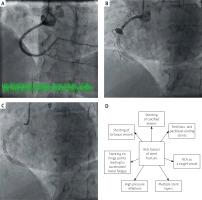

Figure 1

A – Angiography of the right coronary artery 13 months prior the present admission; B – Coronary angiography demonstrating an aneurysm of the right coronary artery with a chronic total occlusion of the vessel and 3 stent fractures (at the level of the aneurysm; on the border between second and third segment of the vessel; and in the distal portion of the vessel); C – The so-called “dry cine” image demonstrating stent fractures; D – Risk factors of stent fracture

There are several risk factors of SF, i.e. stenting of RCA, longer stents, overlapping stents resulting in hinge movements, stenting of calcified lesions, high pressure deployment, and sirolimus- and paclitaxel-eluting stent implantation [1–3] (Figure 1 D). SF can be diagnosed with the use of intravascular imaging modalities, multislice CT, and sometimes by enhanced stent visualisation software tools (e.g. StentBoost or ClearStent) [4]. In the present case, SF was apparent on ordinary cine angiography without using high-resolution software protocols.